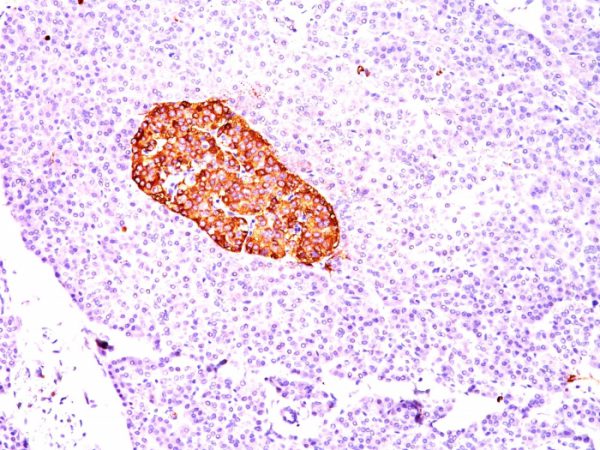

Formalin-fixed, paraffin-embedded human Pancreas stained with Chromogranin A Mouse Monoclonal Antibody (CGA/414).

Chromogranin A is present in neuroendocrine cells throughout the body, including the neuroendocrine cells of the large and small intestine, adrenal medulla and pancreatic islets. It is an excellent marker for carcinoid tumors, pheochromocytomas, paragangliomas, and other neuroendocrine tumors. Co-expression of chromogranin A and neuron specific enolase (NSE) is common in neuroendocrine neoplasms. Reportedly, co-expression of certain keratins and chromogranin indicates neuroendocrine lineage. The presence of strong anti-chromogranin staining and absence of anti-keratin staining should raise the possibility of paraganglioma. The co-expression of chromogranin and NSE is typical of neuroendocrine neoplasms. Most pituitary adenomas and prolactinomas readily express chromogranin.